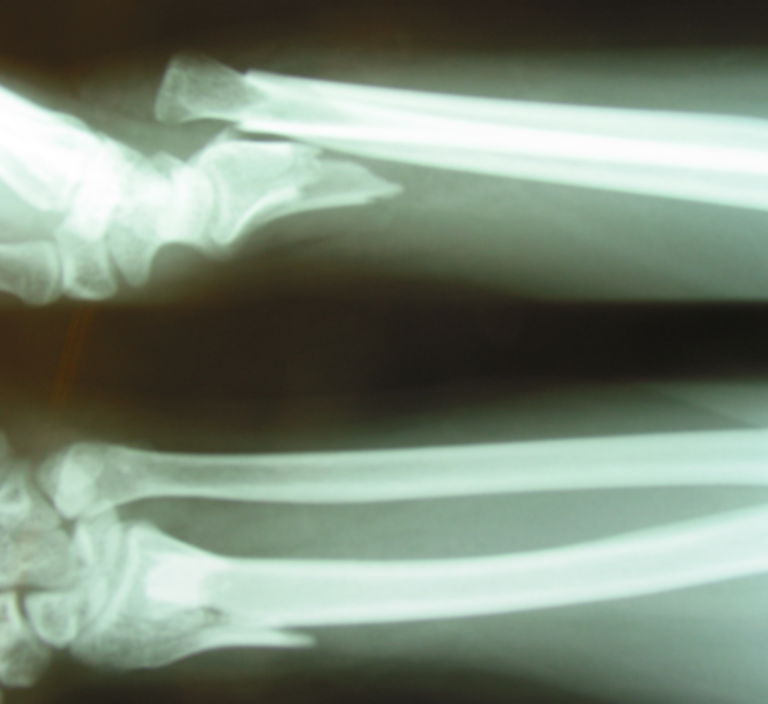

The usual mechanism is high energy and thought to involve axial force through a hyper-pronated forearm. Galeazzis Fracture Adults A Galeazzi fracture is a fracture of the middle to distal third of the radius and either a dislocation or subluxation of the distal radio-ulnar joint DRUJ.

The injury disrupts the forearm axis joint. Qui troverete recensioni di smartphone racconti di viaggi e tutto ciò che ha a che fare con le mie passioni. Diagnosis can be suspected with a distal radius fracture with widening of the radioulnar joint on AP wrist radiographs and volardorsal subluxation of the radioulnar joint on lateral wrist radiographs.

Share your videos with friends family and the world. Architetto amante della tecnologia delle auto anche elettriche e della buona cucina. A galeazzi fracture is a distal 13 radial shaft fracture with an associated distal radioulnar joint DRUJ injury.

The Galeazzi fracture-dislocation as shown in the image below is an injury pattern involving a radial shaft fracture with associated dislocation of the distal radioulnar joint DRUJ.